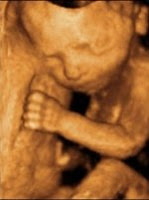

Doppler İncelemelerinin Bebek Üzerine Zararlı Etkileri Var mıdır? Doppler Ultrason, ses dalgaları ile yapılan bir tetkik şeklidir. Doppler Ultrason, ultrason cihazlarının içinde bulunan bir modalitedir.  Amaç; damar içindeki kan akımını değerlendirmektir. Bu şekilde birtakım ekstra değerlendirmeler yapılabilmektedir. Doppler Ultrason bebeğe zararlı değildir. Yalnızca çok uzun süre bakılmaması önerilir. Çünkü bebeğin dokularında ısınmaya neden olabilir. Anne Karnındaki Bebekler Anne karnındaki...

Ultrasonla cinsiyet ne zaman anlaşılabilir? Ultrasonla cinsiyet ne zaman anlaşılabilir? Cinsiyetin dış görünüşü 11. hafta civarında farklılaşmaya başlar bu konuda tecrübeli bir Radyoloji Uzmanı cinsiyeti bu haftada tespit edebilir. Ancak ekseriyetle 15-20 haftalarda ultrasonla daha net biçimde ayırt edilmektedir. Tabi bunda her zaman bir yanılma payı bulunur. Bununla birlikte bazen bebeğin duruşundan dolayı cinsiyet tespitini yapmak hiç olası olmayabilir. Böylesi durumlarda anneyi kaldırmak v...

Genellikle 18-22. haftalar arası Ayrıntılı Gebe Ultrasonografisi yapılır. Bunun dışında erken gebelik haftalarında gebelik kesesinin durumunun incelenmesi, fetüsün (bebeğin) kalp atışlarının değerlendirilmesi amacıyla; ileri gebelik haftalarında da fetüsün genel durumunun değerlendirilmesi ve/veya Ayrıntılı Ultrasonografide tespit edilen anomalilerin takibi açısından (koroid pleksus kisti, böbrek pelvis genişliğinin takibi, barsak parlaklığının takibi, ayrıntılı incelemede pozisyon nedeniyle gör...